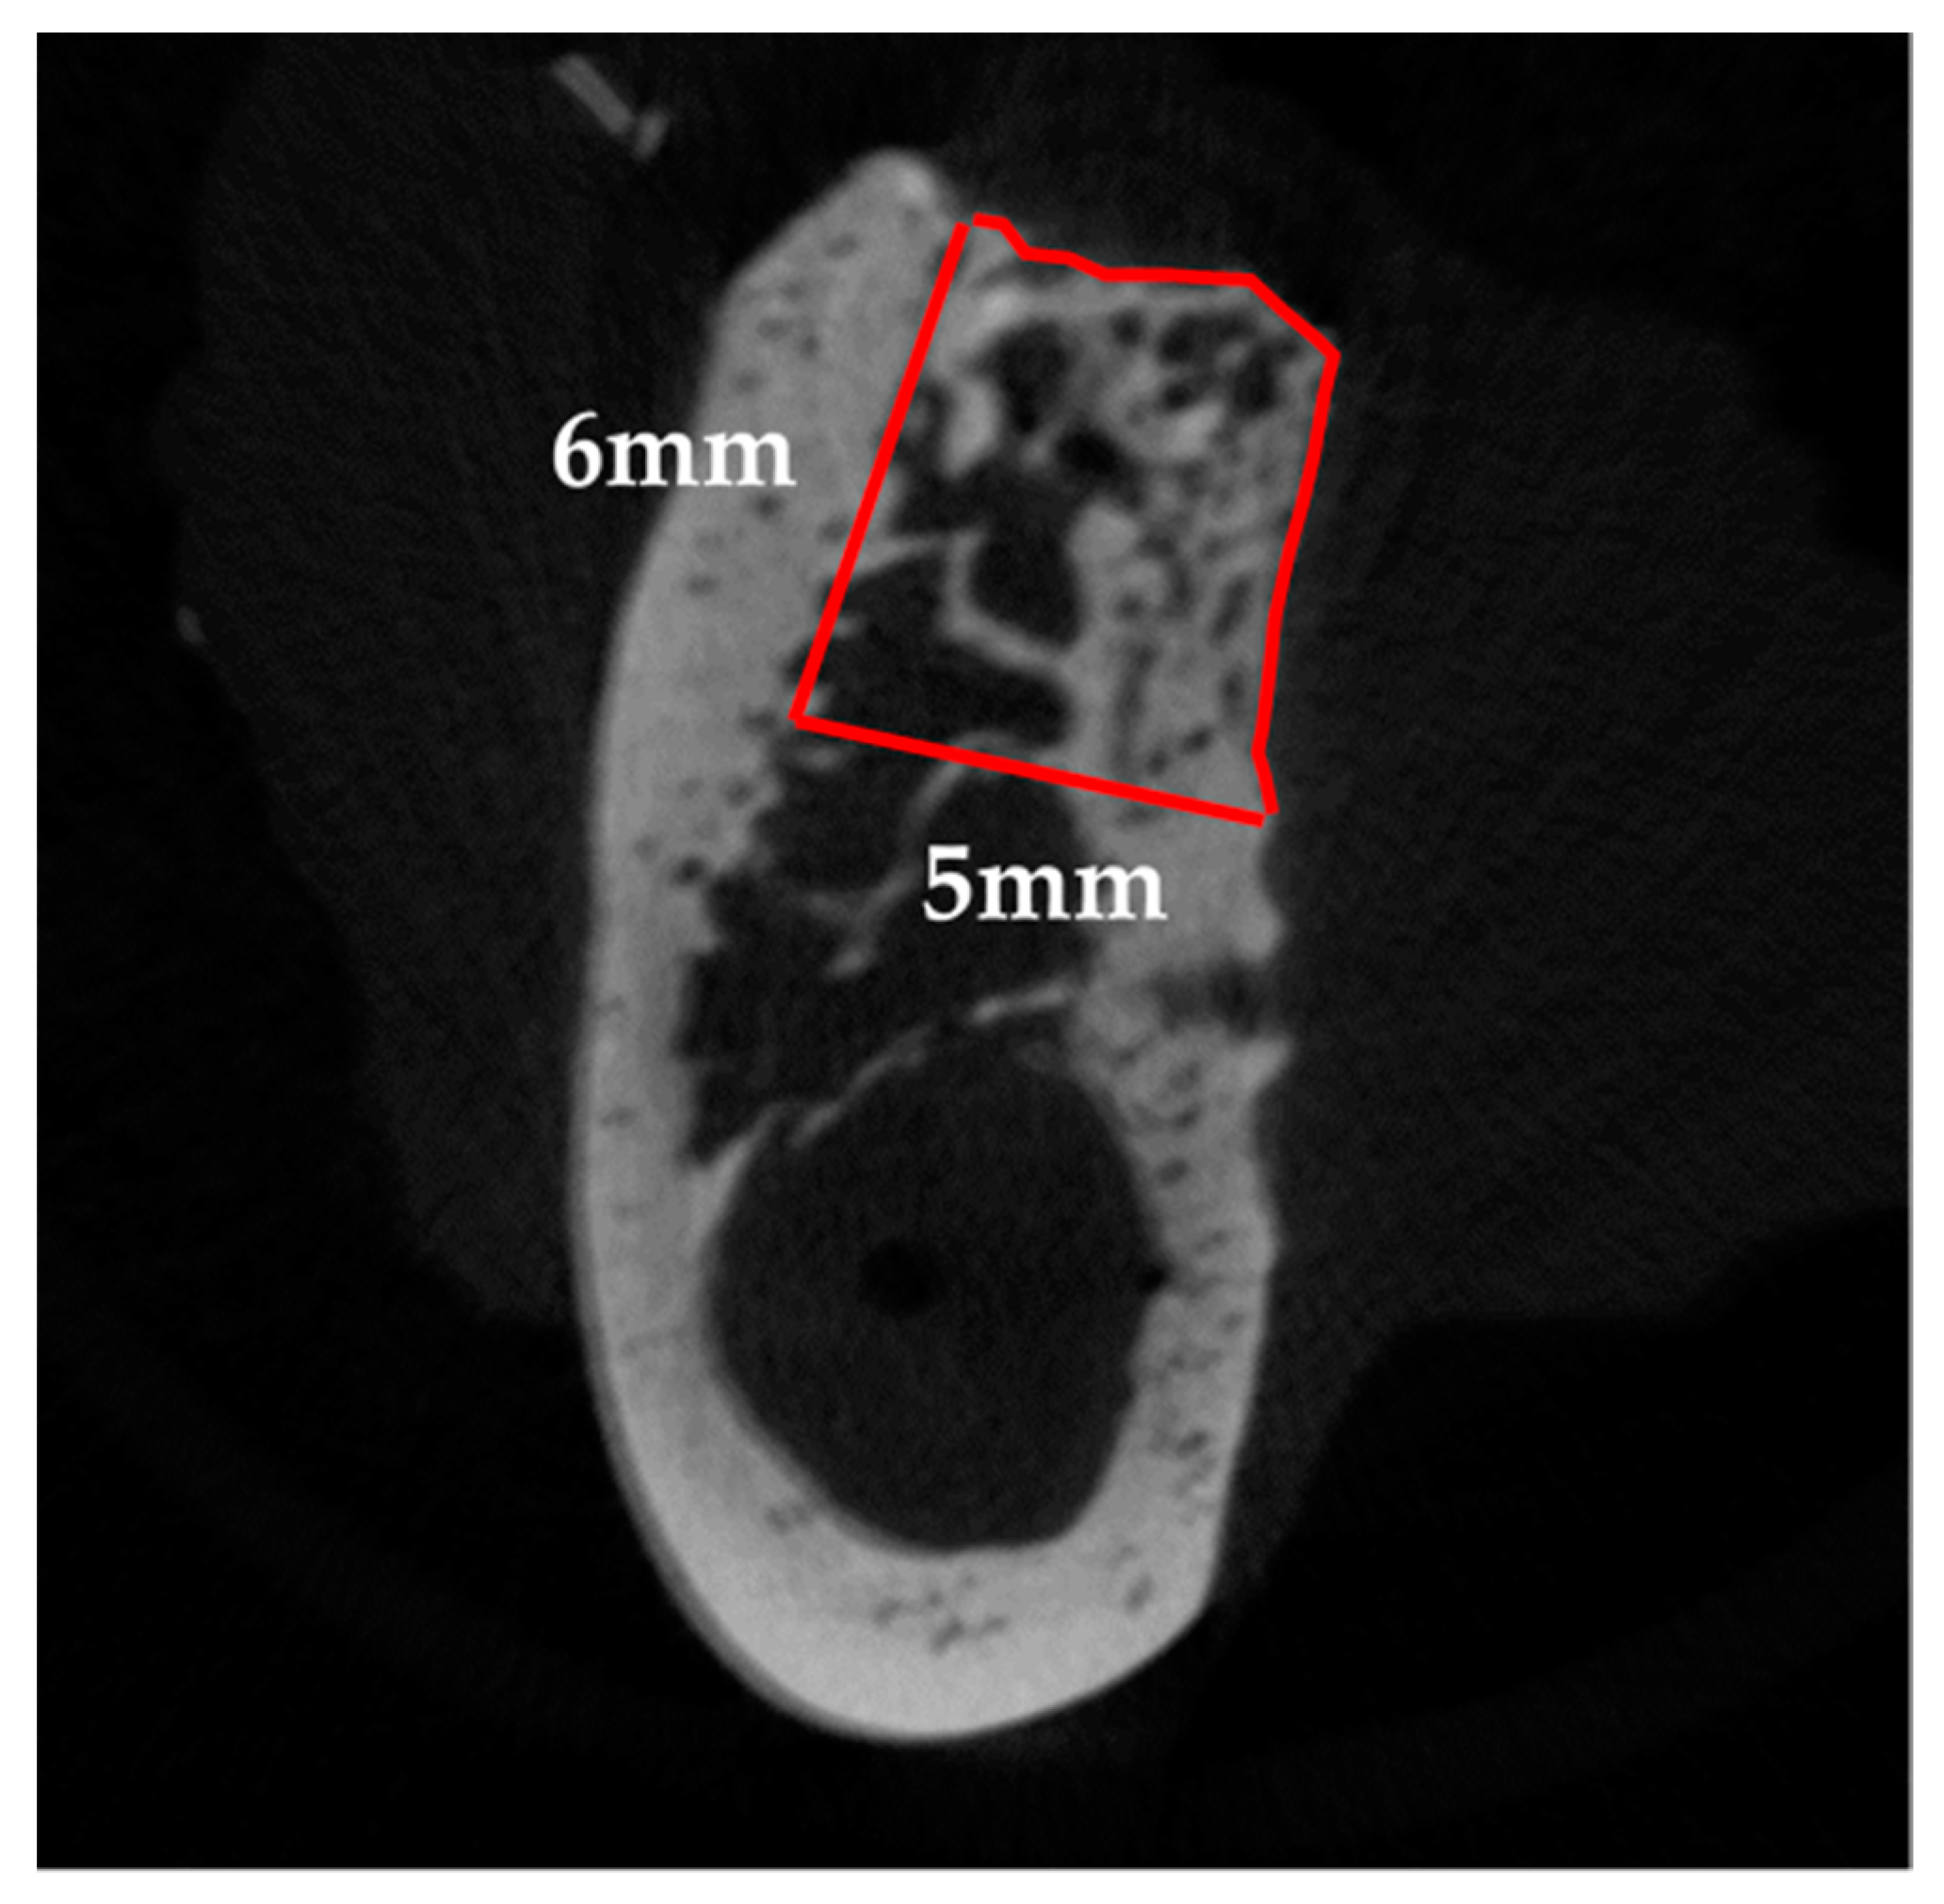

CTAn (ver. 1.15; Bruker Corp.) was used to perform 3D analysis, and to distinguish mineralized tissue, the Otsu algorithm was used to select a threshold of 659 mgHA/mL across all samples. First, the mid-section of the bone defect was determined on the 3D images by referring to the distance from the cervical portion of P1 and M2, and the center of the mental foramen to the edge of the bone defect measured during surgery, as well as the dental radiographs taken immediately after surgery. The two sections were subsequently identified as the mesio-distal limit of the bone defect, 12 mm away from the mid-section, mesially and distally. After identifying the border between the bone defect and the host bone in these sections, the range surrounded by the linear margin of the bone defect (6 mm in height with a 5-mm base) and perimeter of the newly formed bone was manually outlined as the region of interest (ROI). Furthermore, the volume interpolated between these ROIs was referred to as the volume of interest (Figure 4). Following that, tissue volume (TV), bone volume (BV), bone volume-to-tissue volume ratio (BV/TV ratio), and BMD were calculated within the bone defect as radiological morphometric indices [19]. Micro-CT analysis was performed as previously described [17,18].

Figure 4.

Radiographic analysis. The red line represents the region of interest (ROI). On the sections, 12 mm away from the mid-section, both mesially and distally, the range surrounded by the linear margin of the bone defect (6-mm height, 5-mm base) and the perimeter of the newly formed bone was manually outlined after identifying the border between the bone defect and the host bone.